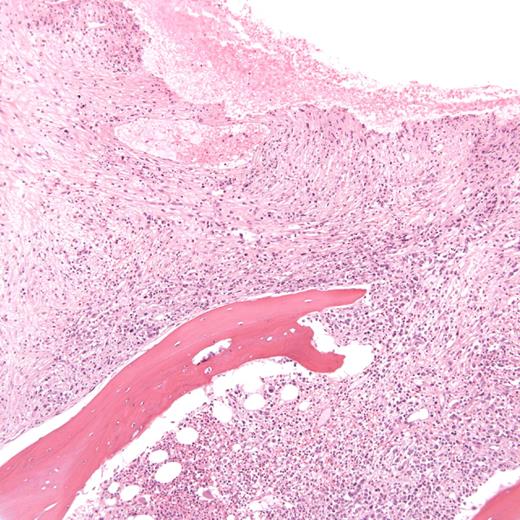

Cytogenetic assessment by fluorescence in situ hybridization of the core biopsy revealed t(9:22) with a deletion of the derivative chromosome 9. Bone marrow aspiration was a dry tap. The trephine biopsy demonstrated acute panmyelosis with myelofibrosis along with abnormal localization of immature precursors with an absence of typical CML megakaryocyte morphology (Figure 1).

Section of bone marrow trephine taken at diagnosis, demonstrating hyperplasia, areas of marked panmyelosis and fibrosis, and clusters of blasts.